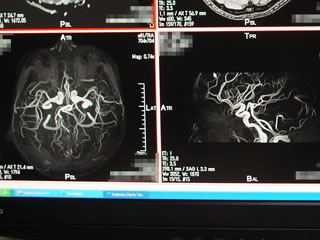

ナントそこには自分の頭の輪切り映像が!

しかも高詳細でかつ3Dでグルグル回転させたり

大きくしたり小さくしたりなんでもござれ。